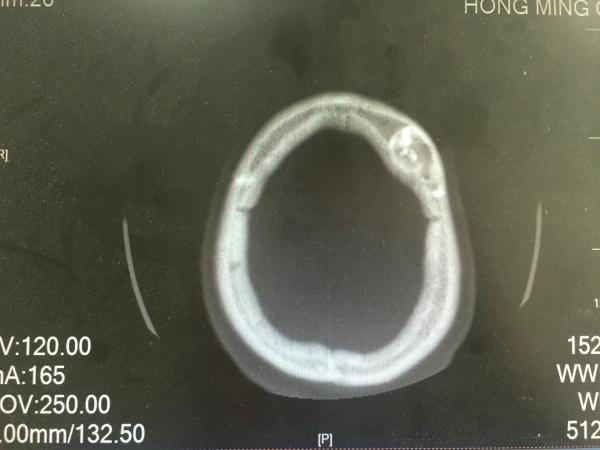

昨夜一位醉酒后外伤的病人,予以头颅CT检查发现的颅骨骨瘤,看着像在板障内,因患者醒酒后家属已送其回家,询问平素无明显不适,故无法跟踪及进一步明确。